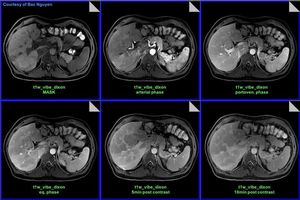

MRI Abdominal Liver Imaging (cirrhosis) @ Siemens 3T Skyra. #Siemens_MRI #mri #cirrhosis #3t #skyra